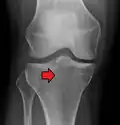

A severe tibial plateau fracture with an associated fibular head fracture

Lateral Tibial Plateau fracture XRay with Depression